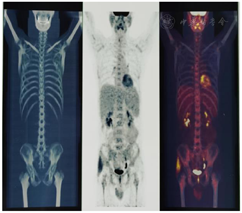

患者,男性,46岁,因"体重下降、腹痛、发热1个月余"入院。患者就诊前1月无明显诱因出现体重下降约10 kg,感腹部胀痛,伴有下午发热,监测体温最高38℃,到当地人民医院就诊,血培养阴性,血常规检查提示三系减少(WBC1.75×109/L、HGB102×109/L、PLT81×109/L),骨髓细胞学提示脾功能亢进不能排外,粒细胞中毒性改变,单核、组织细胞比例轻度升高。骨髓活检增生活跃,三系增生可,未见明显异型细胞。腹部CT检查提示脾脏增大并多发占位病灶,给予抗细菌治疗后患者仍发热,因患者有HIV感染及慢性丙型病毒性肝炎病史,建议到我院就诊。到我院就诊前行PET-CT检查脾大并密度不均,肝S4结节;肝门区、肝胃间隙、下腔静脉及腹主动脉周围、右下腹肠系膜、右侧腮腺区、右侧胸锁乳头肌外缘等部位多发淋巴结,代谢增高;右侧髂骨、右侧髋臼、左侧耻骨及双侧股骨多发代谢性增高灶,以上考虑恶性肿瘤,淋巴瘤浸润可能(图1)。结核性脑膜炎以HRE(异烟肼、利福平、乙胺丁醇)抗结核治疗(到我科就诊时抗结核治疗已经6个月),未抗丙肝治疗,联合抗反转录病毒治疗方案为替诺福韦(TDF)+拉米夫定(3TC)+多替拉韦(DTG)。门诊以"1.恶性肿瘤可能;2.结核性脑膜炎;3.慢性丙型病毒性肝炎;4.AID"收住我科。入院体格检查:T37.5℃,P89次/min,R18次/min,BP103/67 mmHg(1 mmHg=0.133 kPa),身高170 cm,体重60 kg,BMI 20.76kg/m2,神志清楚,浅表淋巴结未触及肿大,脾下缘于左肋缘下5 cm处触及,质地硬,表面光滑。